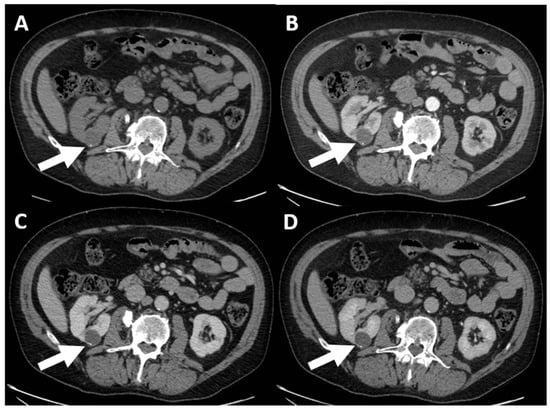

- (e) Class IV: clearly malignant cystic mass, which includes masses characterized by the presence of one or more enhancing nodules (≥4 mm convex protrusion with obtuse margins, or a convex protrusion of any size that has acute margins). A Bosniak IV mass (Figure 5) has a malignancy rate of about 90% and therefore requires urologic consultation to perform partial or total nephrectomy [100].